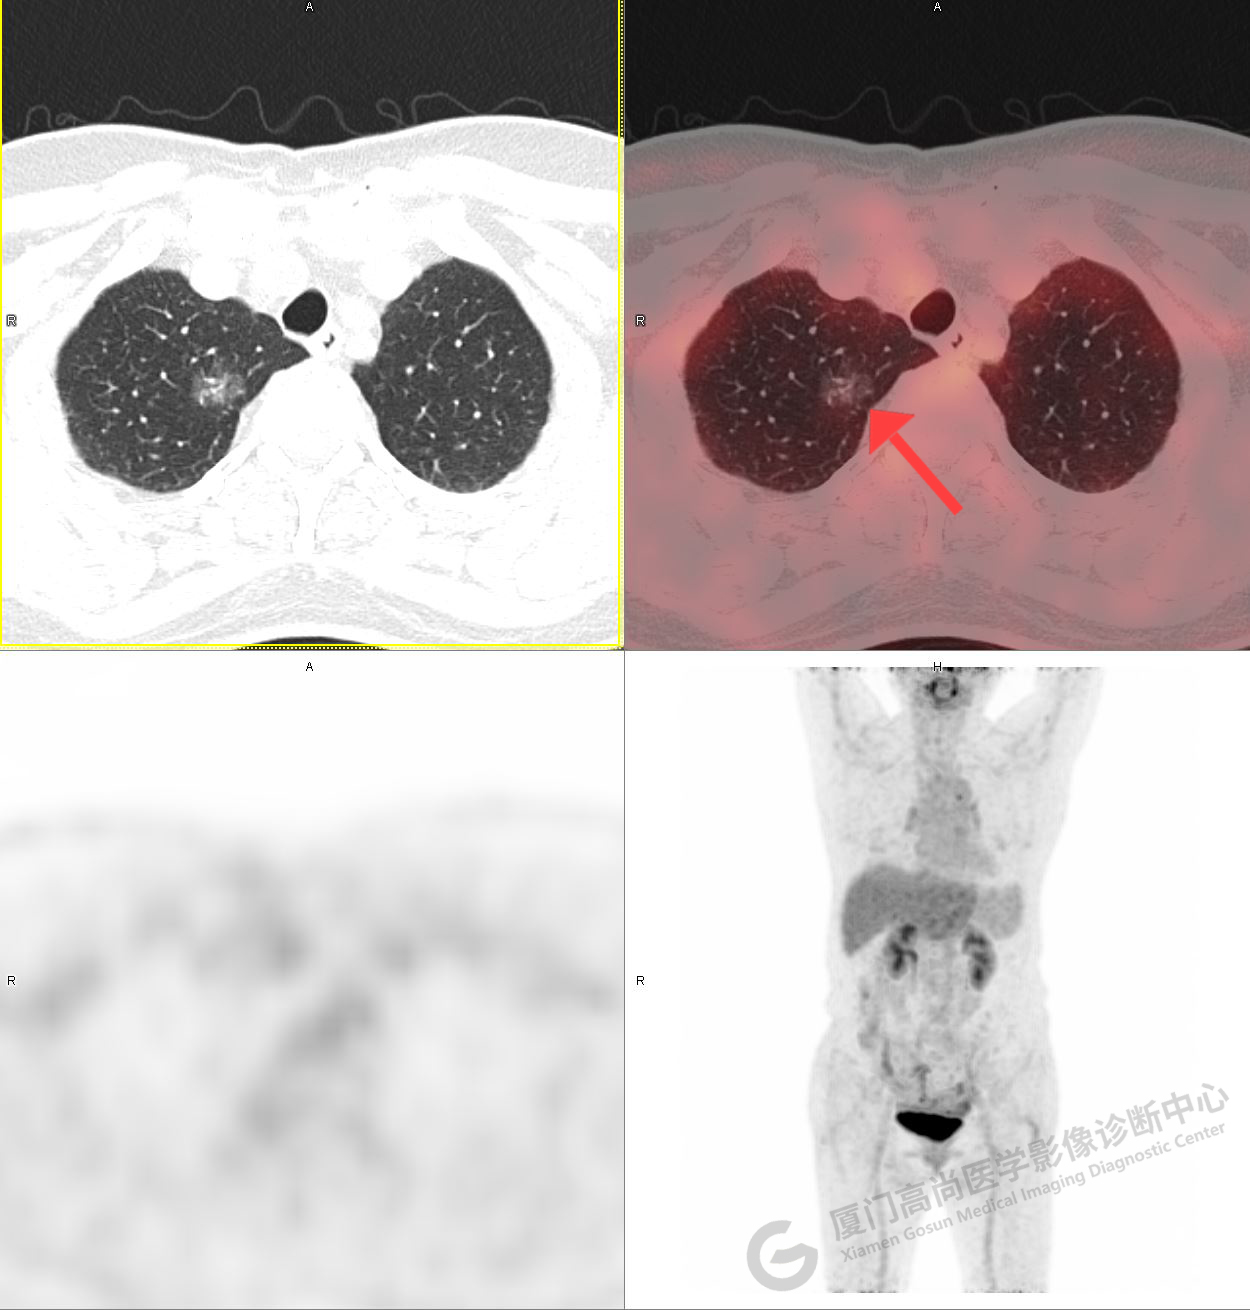

PET/CT影像圖

圖1

圖2

PET/CT示:右肺上葉尖段混雜密度結(jié)節(jié),代謝不高,考慮為早期肺癌(微浸潤腺癌),建議病理學(xué)檢查。

病理證實(shí)是肺腺癌。